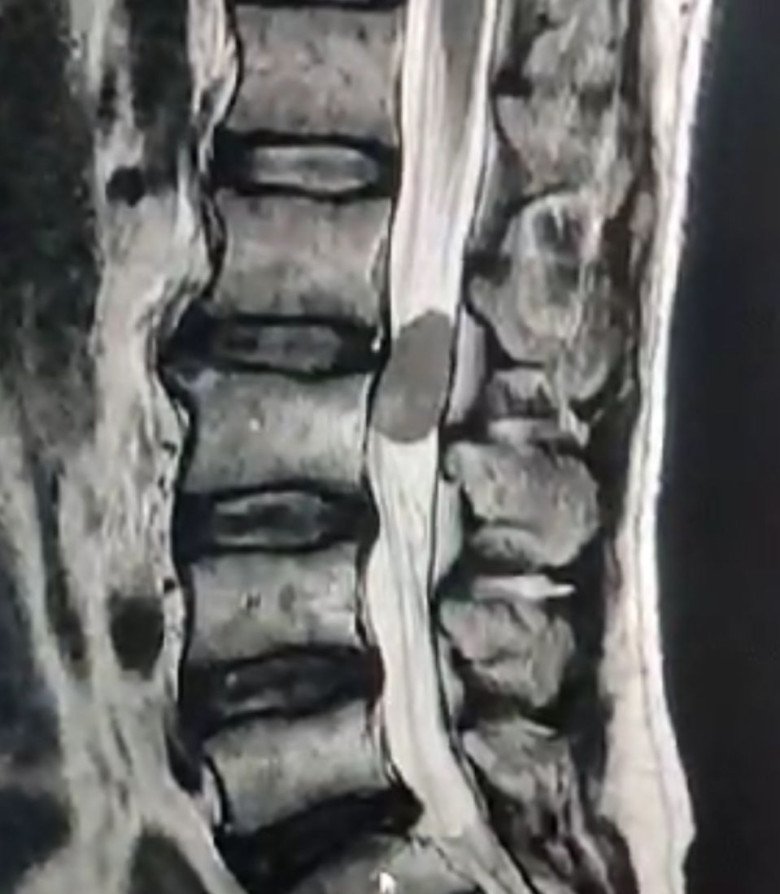

नावापारा मड़वारानी निवासी राज कुमार 40वर्षीय को रीढ़ की हड्डी में कई दिन से दर्द हो रहा था। धीरे-धीरे दर्द बढ़ता गया और अचानक असहनीय दर्द के साथ चक्कर आने की भी शिकायत बढ़ने लगी। परेशान परिजन कई अस्पतालों का चक्कर लगाते रहे लेकिन मरीज को कोई आराम नहीं मिला और वह काफी कमजोर होने लगा। कमर के नीचे के हिस्से ने काम करना बंद कर दिया,उसके दोनों पैरों को लकवा मार चुका था जिससे चलने-फिरने में असहाय हो गया। सब जगह से थक- हार कर परिजन मरीज को उसी हालत में लेकर न्यू कोरबा हॉस्पिटल पहुंचे। मरीज की गंभीर स्थिति को देखते हुए आईसीयू में रखा गया। रीढ़ के हड्डी का एमआरआई करने पर पता चला कि एल-2 व एल-3 के बीचों बीच के हिस्से में 5 सेंटीमीटर के आकार का गांठ बना हुआ था, गांठ को परिवार के लोग देखकर हैरान रह गए। परिजनों ने तब राहत की सांस ली जब डॉ. मित्तल ने ऑपरेशन हो जाने की बात कही। डॉ. मित्तल ने एनेस्थेटिस्ट डॉ. रोहित मजुमदार, देवेंद्र मिश्रा, राम कोसले सहित सहयोगी टीम के साथ ऑपरेशन किया। 7 घण्टे तक चला ऑपरेशन पूर्णत: सफल रहा और मरीज धीरे-धीरे सामान्य होने लगा। फिजियोथैरेपिस्ट डॉ. यशा मित्तल व डॉ. अमन श्रीवास्तव के प्रयास से मरीज को चलाया-फिराया गया। मरीज को अस्पताल से छुट्टी दे दी गई है और अब वह स्वस्थ है। मरीज के परिजनों ने डॉ. डी.एच. मित्तल सहित उनकी टीम का आभार जताया है।